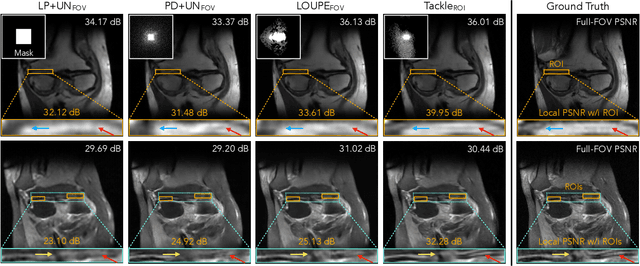

Abstract:Compressed sensing magnetic resonance imaging (CS-MRI) seeks to recover visual information from subsampled measurements for diagnostic tasks. Traditional CS-MRI methods often separately address measurement subsampling, image reconstruction, and task prediction, resulting in suboptimal end-to-end performance. In this work, we propose TACKLE as a unified framework for designing CS-MRI systems tailored to specific tasks. Leveraging recent co-design techniques, TACKLE jointly optimizes subsampling, reconstruction, and prediction strategies to enhance the performance on the downstream task. Our results on multiple public MRI datasets show that the proposed framework achieves improved performance on various tasks over traditional CS-MRI methods. We also evaluate the generalization ability of TACKLE by experimentally collecting a new dataset using different acquisition setups from the training data. Without additional fine-tuning, TACKLE functions robustly and leads to both numerical and visual improvements.